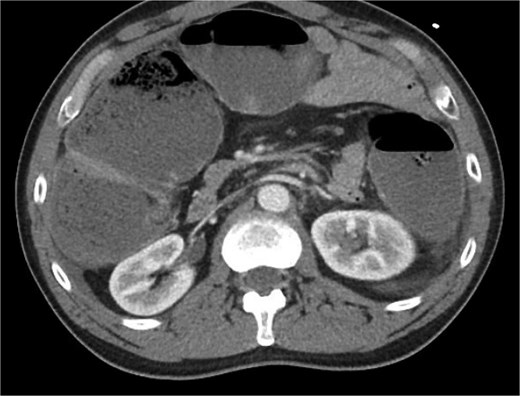

The patient was a 49-year-old male with a past medical history of anxiety and constipation who originally presented to the emergency department complaining of 1 day of worsening generalized abdominal pain, obstipation, nausea, and chills. Of note, he had undergone a colonoscopy 3 months prior to presentation, where two benign polyps were removed. There were no signs of inflammatory bowel disease. Upon examination, he was noted to be tachycardic to 130, with a blood pressure of 90/70 after 2 L of intravenous fluid resuscitation. His abdomen was distended and diffusely tender with peritoneal signs. Laboratory analysis showed a white blood cell count of 26 000, creatinine of 1.8, and a lactic acid of 7.9. A CT of the abdomen/pelvis revealed a cecum of 12 cm filled with liquid stool, but no pneumoperitoneum, pneumatosis, or colonic wall thickening. Figures 1 and 2 demonstrate the axial and coronal images of the dilated colon, respectively.

Axial imaging demonstrating significant colonic dilation. There was no evidence of pneumatosis or pneumoperitoneum.